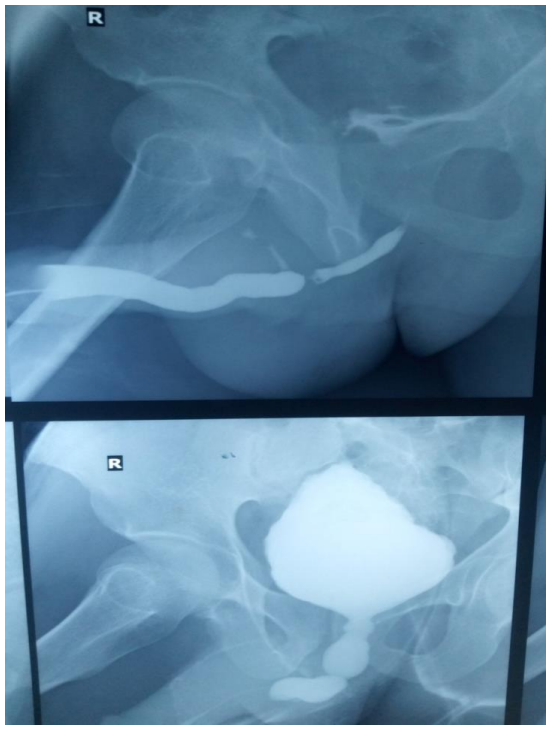

Пациента направили в отделение радиологии для сканирования мочевого пузыря и поиска подобных физических аномалий. Чтобы визуализировать мочевой пузырь на рентгеновских снимках, рентгенологи ввели через брюшной катетер контрастное вещество, чувствительное к рентгеновским лучам. Снимки показали, что мочевой пузырь раздулся у основания, образовав заострённую верхушку.

Диагноз: Это состояние известно как «мочевой пузырь в форме рождественской ели» или «шишковидный» мочевой пузырь — из-за характерного внешнего вида.

Рентген подтвердил, что отток мочи из органа был заблокирован. Однако при более внимательном изучении самого мочевого пузыря не было обнаружено его внутренних патологий, таких как опухоль или камни. Это заставило врачей предположить, что препятствие может находиться в другом месте.